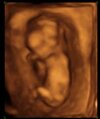

To nasz (na 99%) Maciuś pod koniec 13 tygodnia. Tylko na koniec badania jak lekarz odpalił 4D to dzidziuś się pogniewał i odwrócił pleckami :D

Maciuś 3D..jpg